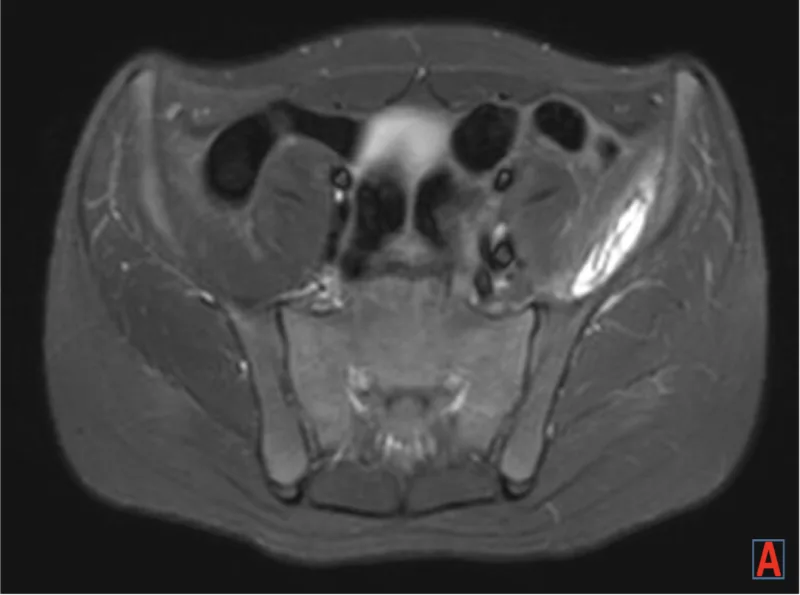

外来に戻ると, 先ほどの仙骨骨折疑い患者さんのMRI結果が到着.

幸い刺青の火傷はなく, 骨折も認めませんでした.

腸骨筋と大殿筋内に血腫を認め, 筋肉内血腫と診断. 歩行困難のため, 入院加療することになりました.

T1強調画像(a)では, 皮下脂肪と同じように白く写り, 脂肪抑制画像(b)では黒く写ります.

脂肪抑制下造影T1強調画像(c)では, 造影効果が認められず, 白くなりません.